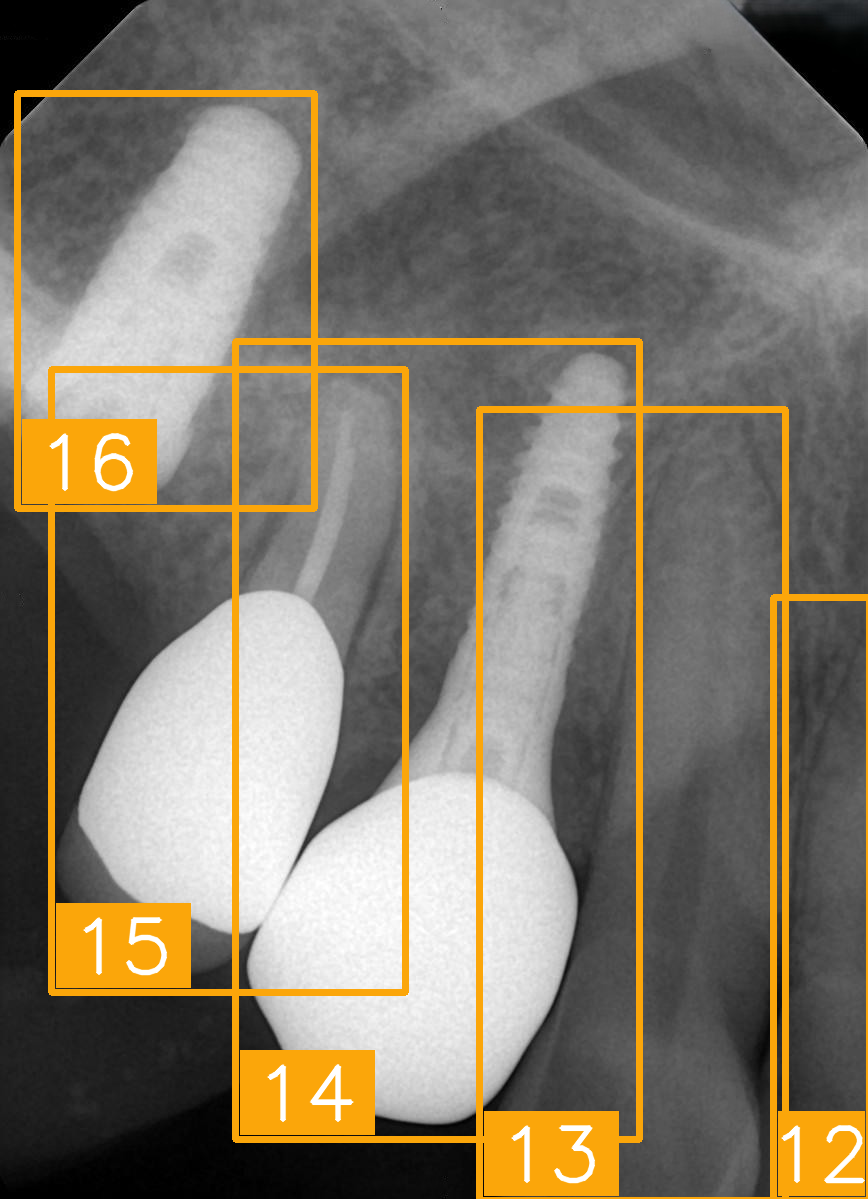

| Number | (e) | (f) | (g) | (h) |

| Condition | Fractured tooth; lower brightness | Overlapping | Implant | Implant |

| PA | ![]() | ![]() | ![]() | ![]() |

| FDI ground truth number | 45, 44, 43 | 32, 33, 34, 35 | 16, 15, 14, 13, 12 | 24, 25, 26 |

| Inference Time | 72.8 ms | 77.2 ms | 70.6 ms | 72.4 ms |